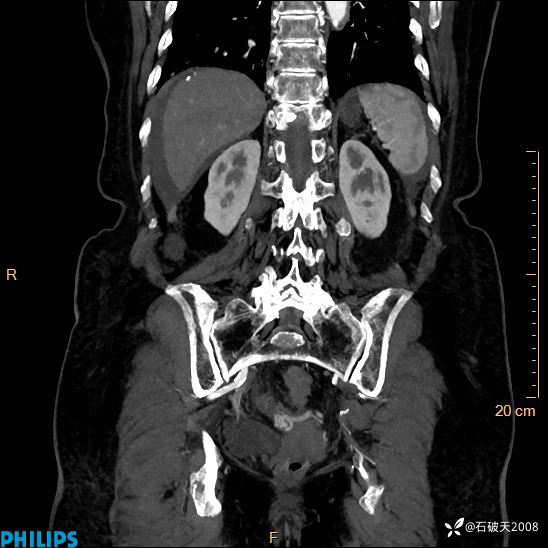

静脉期